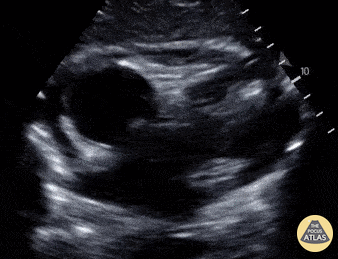

Pediatrics - Pericardial Effusion

An 8-year-old male presented with a 1 day history of fever and chest pain. Cardiac POCUS shown here revealed a pericardial effusion; he was later started on steroids for the same enabling hospital discharge on hospital day #2. Amar Singh, MD. University of Louisville